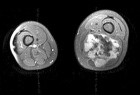

J.G. - 14 year old male c/o left posterior thigh mass for eight months. His mother noticed the mass, but no ecchymosis, after he fell while running hurdles. He complains of pain only when running long distances, and with prolonged pressure. It has decreased in size only minimally. No F/C.